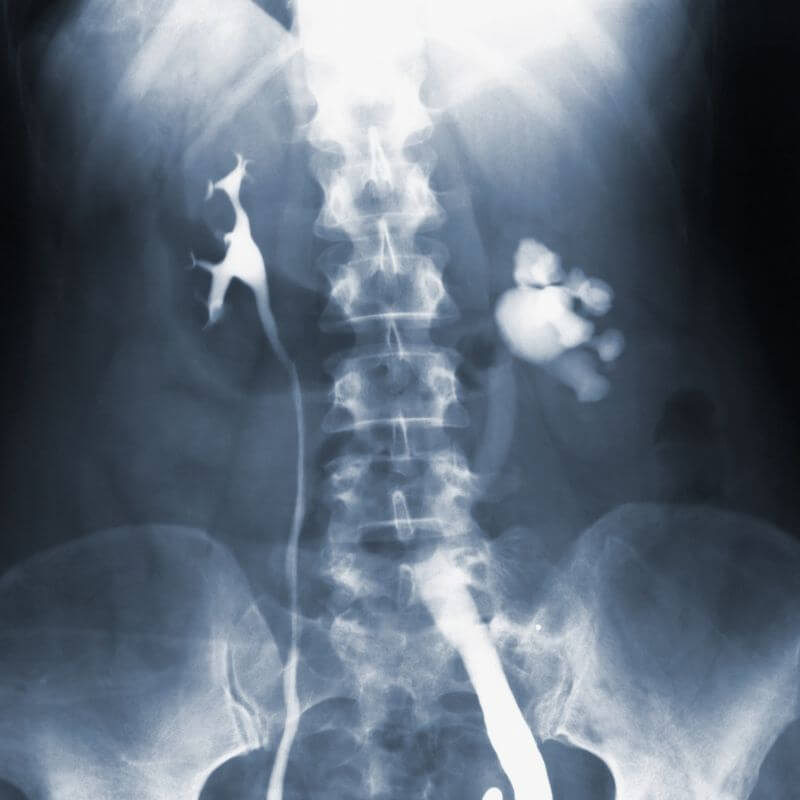

Los rayos X son un tipo de radiación electromagnética similar a la luz visible. Sin embargo, a diferencia de la luz, estos rayos tienen mayor